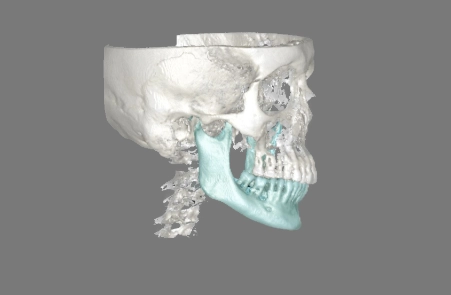

Wir nutzen DVT- oder 3D-Aufnahmen, um Ihren Kiefer präzise darzustellen und den idealen Platz für jeden Pin zu bestimmen.

Wir analysieren Knochen, Nervenbahnen und Wurzeln, um die sichersten Pin-Zonen festzulegen.

Wir nutzen Software, um die präzise Platzierung der Pins zu planen – für eine optimale Kraftrichtung, abgestimmt auf Ihre Anatomie und Bewegungsziele.